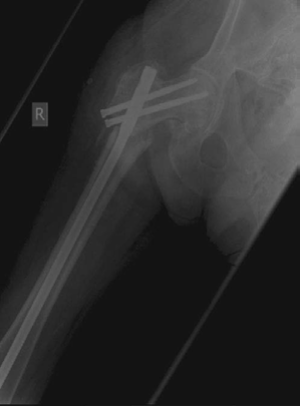

Minute 2 EXAMINER : This woman’s fracture was managed elsewhere and presents during your on-call week with this complication. Can you explain what has happened? (Figures 8.10 and 8.11.) CANDIDATE : This lady was treated with a fixed-angled locking plate. Two things are perhaps responsible for this failure: biomechanics and biology.

Looking at the postoperative radiograph, there is a gap at the fracture site especially medially. The fixed-angled device has been used with locking screws with five screws on either side of the fracture, which will make it a very rigid implant. This will prevent any micro-motion necessary for callus formation. In addition, there is a fracture gap and lack of compression that will preclude primary bone union. This has resulted in a delayed union/atrophic non-union at the fracture site.

The implant has been under constant biomechanical load, which has led to the fatigue failure of the implant. In this particular design there is a stress riser at the junction of the last proximal locking hole and the tapered part of the plate, which dictates the failure point in the implant. In addition, the plating device is applied on the lateral aspect of the femur increasing the lever arm for the moment of force as compared with a cephalomedullary device, which further puts the fixed-angle

plating device in this position at a biomechanical disadvantage. Similar results were reported with the use of compression hip screw and 95o plate.2 In this type of fracture an intramedullary device has better results and biomechanical stability.